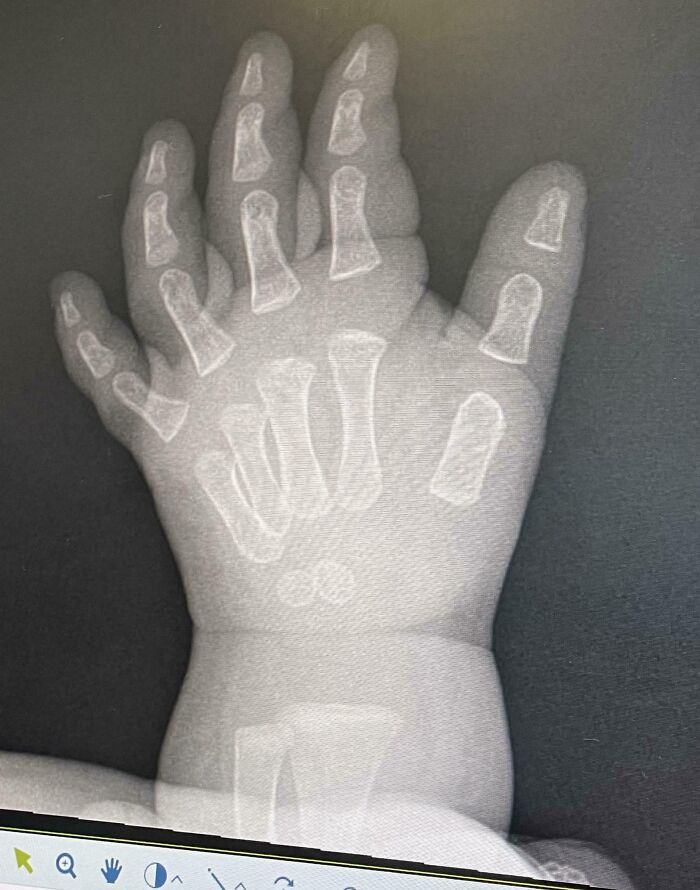

#3 Did You Know: An X-Ray Of A Baby’s Hand Makes It Look Like Their Bones Are Just Kinda Floating Around In There

Our 11-month-old somehow hurt her hand/wrist, and in trying to figure out what was wrong we got some x-rays. Unfortunately nothing conclusive came from the scans, but I thought the x ray itself was mildly interesting. Baby girl is going to be fine, apparently infants have Wolverine-like regenerative powers.